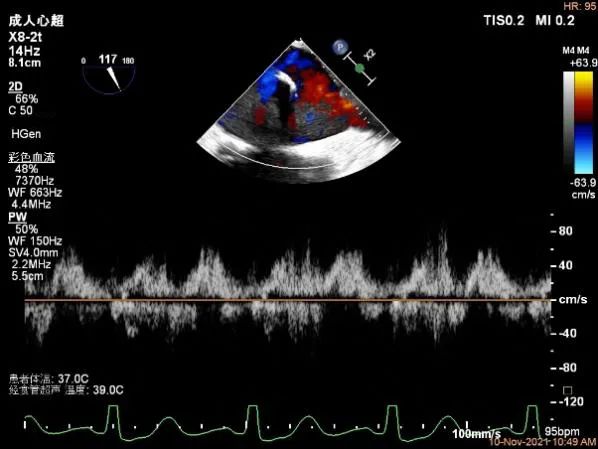

肺静脉血流频谱逐渐恢复正向

肺静脉血流频谱恢复正向

肺静脉血流频谱完全正向